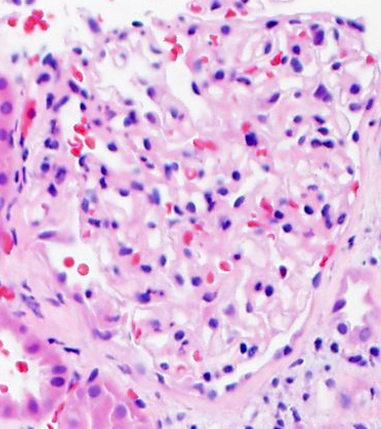

1. Hematoxylin & Eosin Stain or H&E: hematoxylin binds to basophilic substances and stains them dark blue/violet (like DNA/RNA) while eosin binds to acidophilic substances and stains them red (like amino acids). The H&E is a principal histochemical stain.

A kidney pathology tip to identify a hypercellular glomerulus: try the chocolate chip cookie analogy (i.e. more chips = more cells)